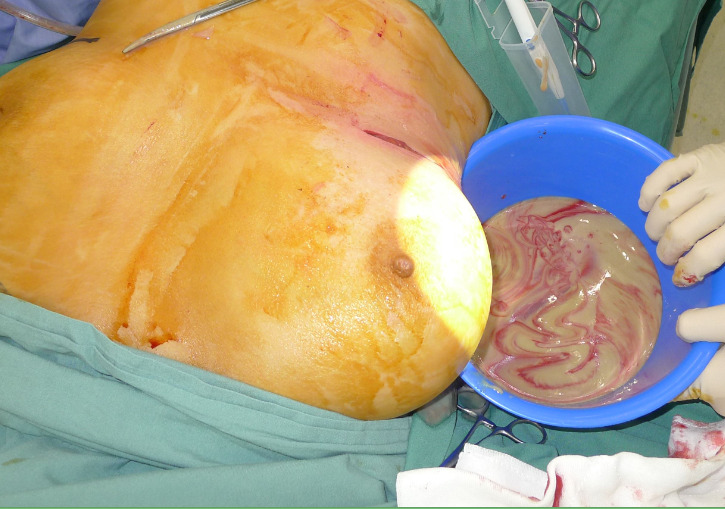

A 53-year-old woman presented with two months of right breast swelling and fevers with a background of bilateral free PAAG filler augmentation in China 14 years earlier. MRI showed free prosthetic material in subglandular and subpectoral pockets on both sides without parenchymal lesions (Figure 1). On examination she had marked swelling and mild erythema of the right breast with elevated inflammatory markers. The patient was taken to theatre the same day for evacuation of the prosthetic filler. Via bilateral infra-mammary incisions, 900 ml of purulent material was evacuated from the right breast (Figure 2) and 300 ml PAAG filler removed from the left breast (Figure 3). Tissue culture, swab culture and capsule histopathology demonstrated scant mix of skin flora. Mycobacterial PCR for tuberculosis was negative. Capsule histopathology from both sides showed fibrous pseudocapsule with extracellular foreign body material and a mixed inflammatory cell infiltrate. The patient completed a six-week oral antibiotic regime and made an uncomplicated recovery.